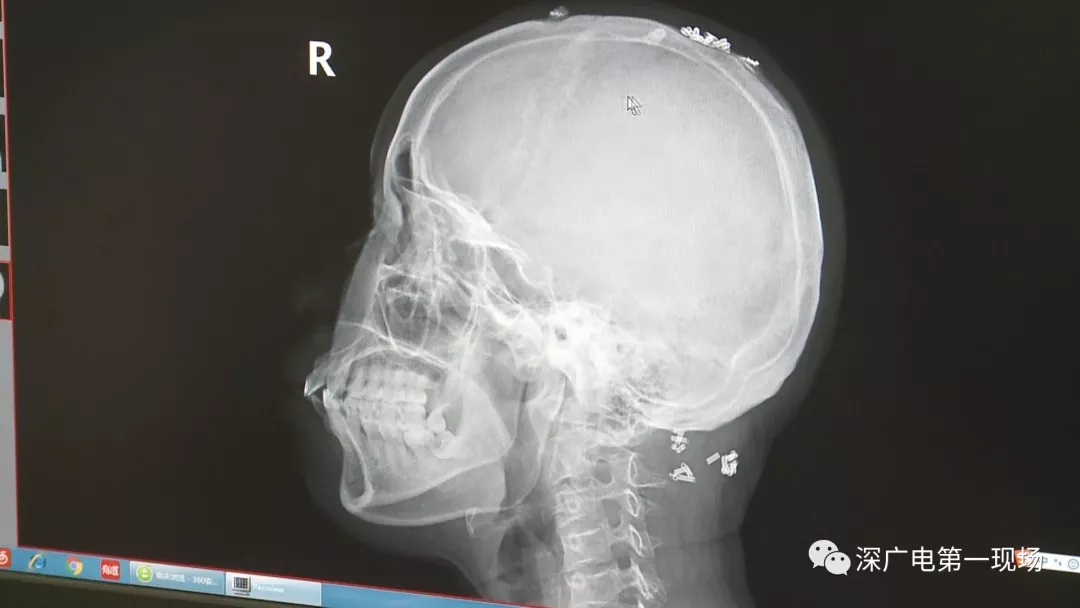

深圳一女子全身被植入彈簧圈,數(shù)量多到驚人!竟是為治這病…

彈簧圈已“寄生”三年

部分形成包塊難以取出

據(jù)了解,這位患者周身的彈簧圈已經(jīng)固定了三年多,因?yàn)榛颊吒杏X(jué)治療效果不好,就來(lái)深圳求醫(yī)。